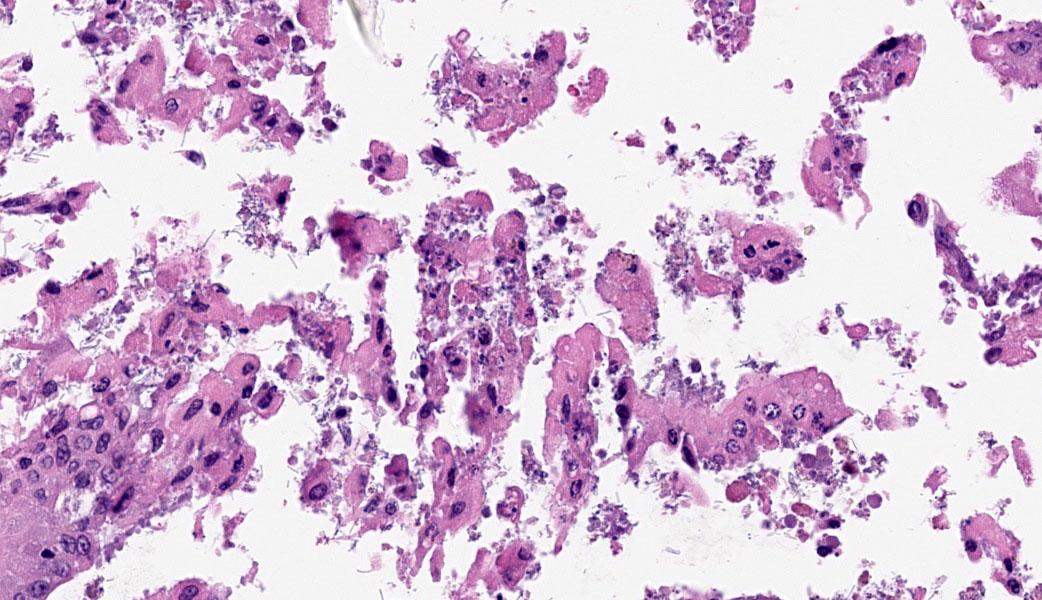

Cecum at ileocecocolic junction: One full-thickness cross sections of cecum at the ileocecocolic junction are examined from each animal (2 total). Diffusely, the submucosa is expanded by clear space (edema) and admixed inflammatory cells (neutrophils, macrophages, lymphocytes, and fewer plasma cells). The lamina propria is multifocally expanded by edema, hemorrhage, the previously mentioned admixed inflammatory cells, and karyorrhectic debris. The overlying epithelium has multifocal erosions and ulcerations with surface necrotic debris and mixed bacterial colonies.

Colon: Colitis, necrotizing, subacute, multifocal, moderate, with volcano lesions, hemorrhage, and severe submucosal edema.

Similar to Case 1, due to the presence of volcano lesions coupled with mucosal ulceration/necrosis and heterophilic inflammation, Dr. Uzal says this is C. difficile until proven otherwise! This case had some solid examples of volcano lesions in which heterophils could be seen exploding out of tiny ulcers in the mucosa.